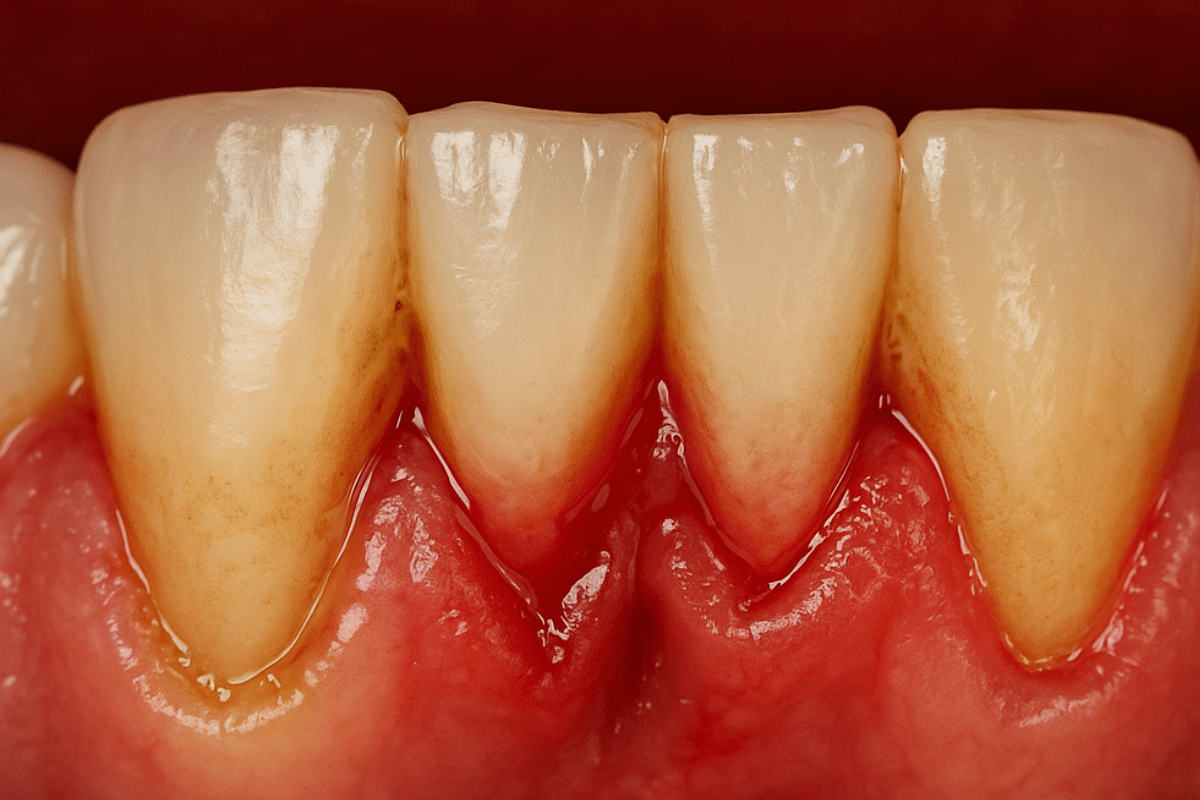

Parodontitis, auch bekannt als Parodontalerkrankung, ist eine chronische Erkrankung, die das Stützgewebe der Zähne betrifft. Sie beginnt mit milden Symptomen wie Zahnfleischbluten beim Zähneputzen, Empfindlichkeit und Mundgeruch. Mit der Zeit zieht sich das Zahnfleisch zurück, wodurch die Zahnwurzeln freigelegt und empfindlich werden.

Wenn es um Erfahrungen mit Parodontitis geht, betonen die meisten Patienten, wie wichtig eine frühe Diagnose ist. Viele bemerkten die ersten Symptome, wie Zahnfleischbluten und Empfindlichkeit, ignorierten sie jedoch. Erst nach dem Auftreten ernsthafterer Probleme suchten sie Hilfe, was die Behandlung erheblich erschwerte.